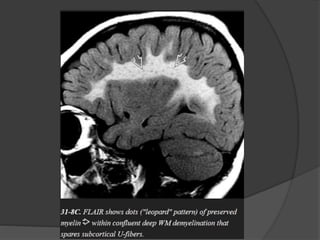

Islands of normal myelin around medullary veins in the WM may produce a

striking "tiger" or "leopard" pattern with linear hypointensities in a sea of

confluent hyperintensity. No enhancement is seen on T1 C+.

The typical MRappearance is confluent, symmetric, butterfly-shaped T2/FLAIR hyperintensity in the periventricular WM. The subcortical U-fibers and cerebellum are typically spared until late in the disease. Islands of normal myelin around medullary veins in the WM may produce a striking "tiger" or "leopard" pattern with linear hypointensities in a sea of confluent hyperintensity. No enhancement is seen on T1 C+. A few cases of MLD have been reported with enlarged, enhancing cranial nerves and/or cauda equina nerve roots. Restricted diffusion is common. MRS typically shows elevated choline with variable increase in myoinositol.